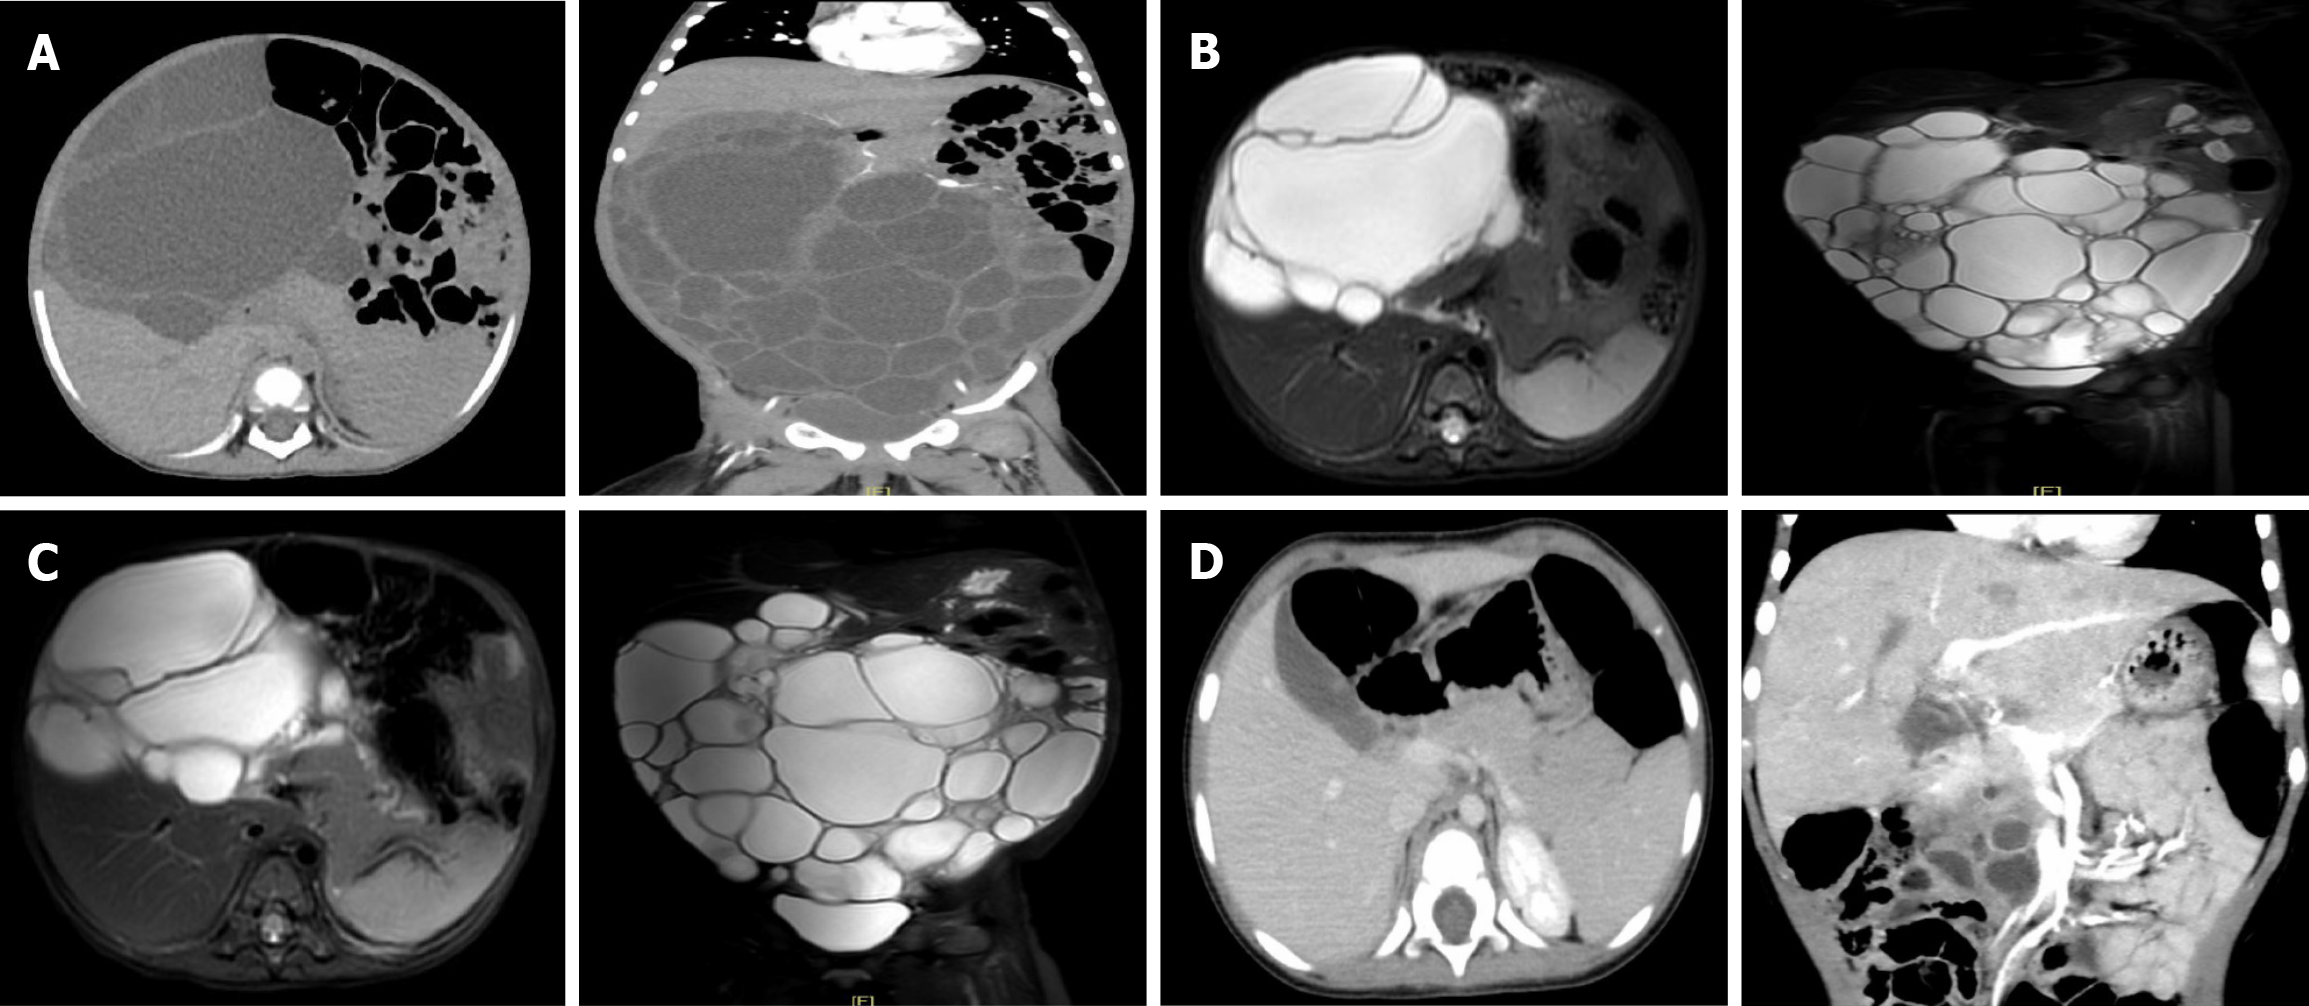

Figure 1 Abdominal computed tomography and magnetic resonance images.

A: Abdominal computed tomography (CT) scan completed on March 22, 2023. Large multiloculated, multiseptated cystic mass (21.7 cm × 16.8 cm × 8.9 cm); B: Abdominal magnetic resonance (MR) completed on April 27, 2023. The size of the cyst was similar to previous CT (18.0 cm × 10.0 cm × 21.0 cm); C: Abdominal MR completed on June 27, 2023. The size of the cyst was similar to previous MR (17.9 cm × 11.0 cm × 21.0 cm); D: Abdominal CT scan completed on February 26, 2024. Pancreatic head cyst was significantly reduced (4.6 cm × 4.3 cm × 2.0 cm).